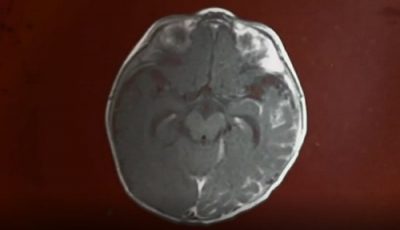

The complexity of brain surgery | Inside the Human Body

The complexity of brain surgery | Inside the Human Body

A little girl, Angelina, requires complex brain surgery in order to alleviate the systoms she is suffering as a resul...